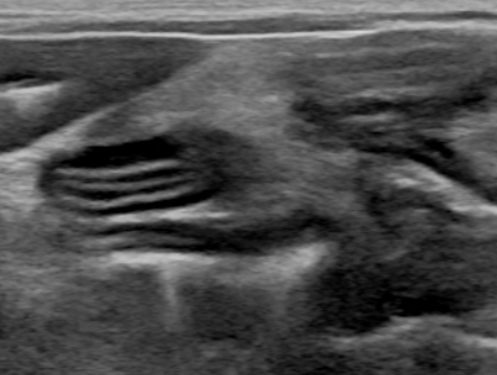

feline IBD(inflammatory bowel disease) cast ultrasonographic image sample

Well-demarcated thickening of the muscular layer with relatively preserved stratified wall structure.